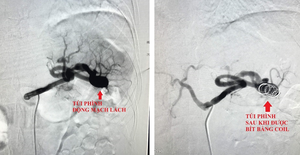

Chụp CT khẩn cấp phát hiện trong bụng bệnh nhân có khối phình động mạch chủ bụng khổng lồ đường kính 9 cm, gấp ba lần bình thường, dấu hiệu vỡ, máu tràn sau phúc mạc.

Khi mở ổ bụng, các bác sĩ đối mặt tình huống căng thẳng hơn dự đoán, máu tràn vào khoang sau phúc mạc. Trong thời gian tính bằng giây, ê kíp nhanh chóng kiểm soát điểm vỡ, kẹp clamp cầm máu tạm thời, đồng thời bảo tồn tối đa các nhánh mạch thận và mạc treo tràng dưới, yếu tố sống còn để phòng suy tạng sau mổ.

Đoạn động mạch bị tổn thương được thay thế bằng ống ghép nhân tạo. Từng đường khâu được thực hiện tỉ mỉ dưới kính vi phẫu, kết hợp keo sinh học để kiểm soát chảy máu.